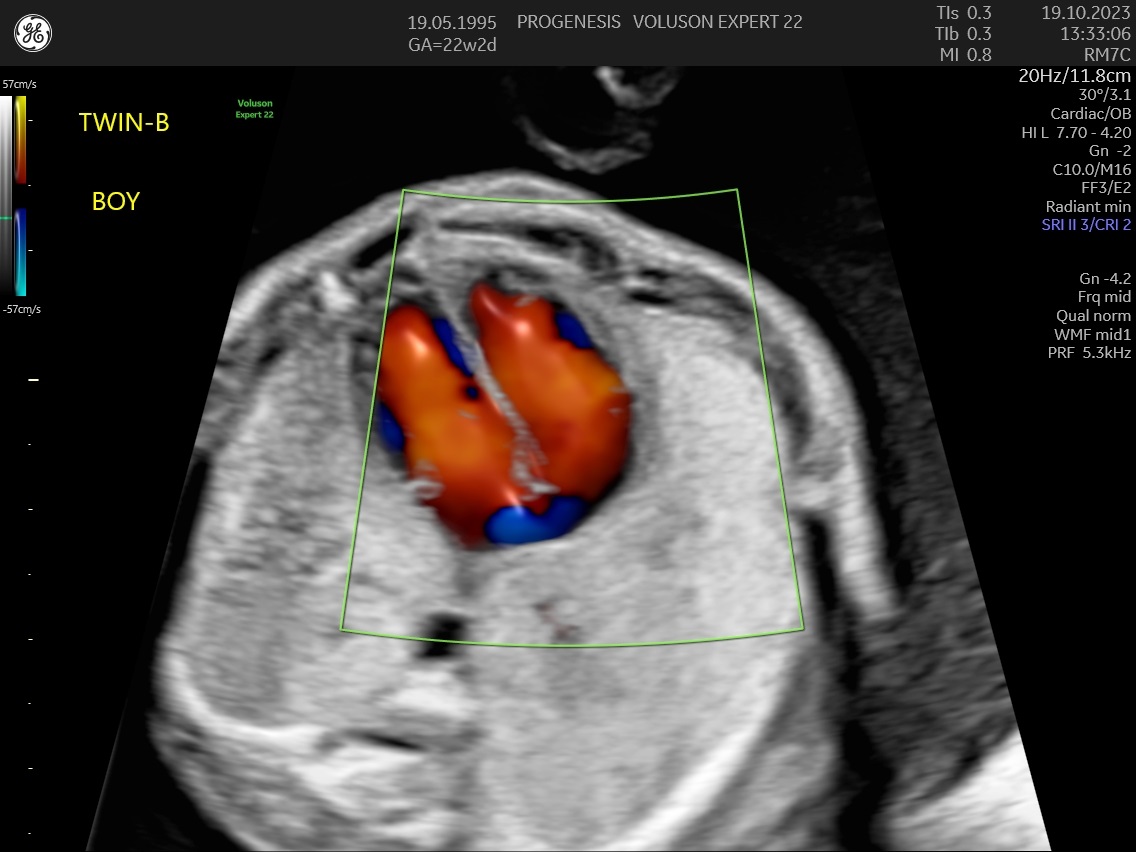

α) Η λεπτομερής αξιολόγηση της εμβρυϊκής ανατομίας, όπου αναγνωρίζονται τυχόν ανατομικές ανωμαλίες.

γ) Ο έλεγχος της ανάπτυξης του εμβρύου, του πλακούντα, του ομφαλίου λώρου και του αμνιακού υγρού.

ε) Ο υπολογισμός της πιθανότητας προεκλαμψίας και ενδομήτριας καθυστέρησης της ανάπτυξης του εμβρύου.

Η μέτρηση των αντιστάσεων στις αρτηρίες της μήτρας, θα εντοπίσει τις μητέρες που έχουν αυξημένη πιθανότητα να εμφανίσουν υπέρταση ή προεκλαμψία στη κύηση ή και πλακουντιακή δυσλειτουργία που θα οδηγήσει σε ελλάτωση της εμβρυϊκής ανάπτυξης (μικρό έμβρυο).